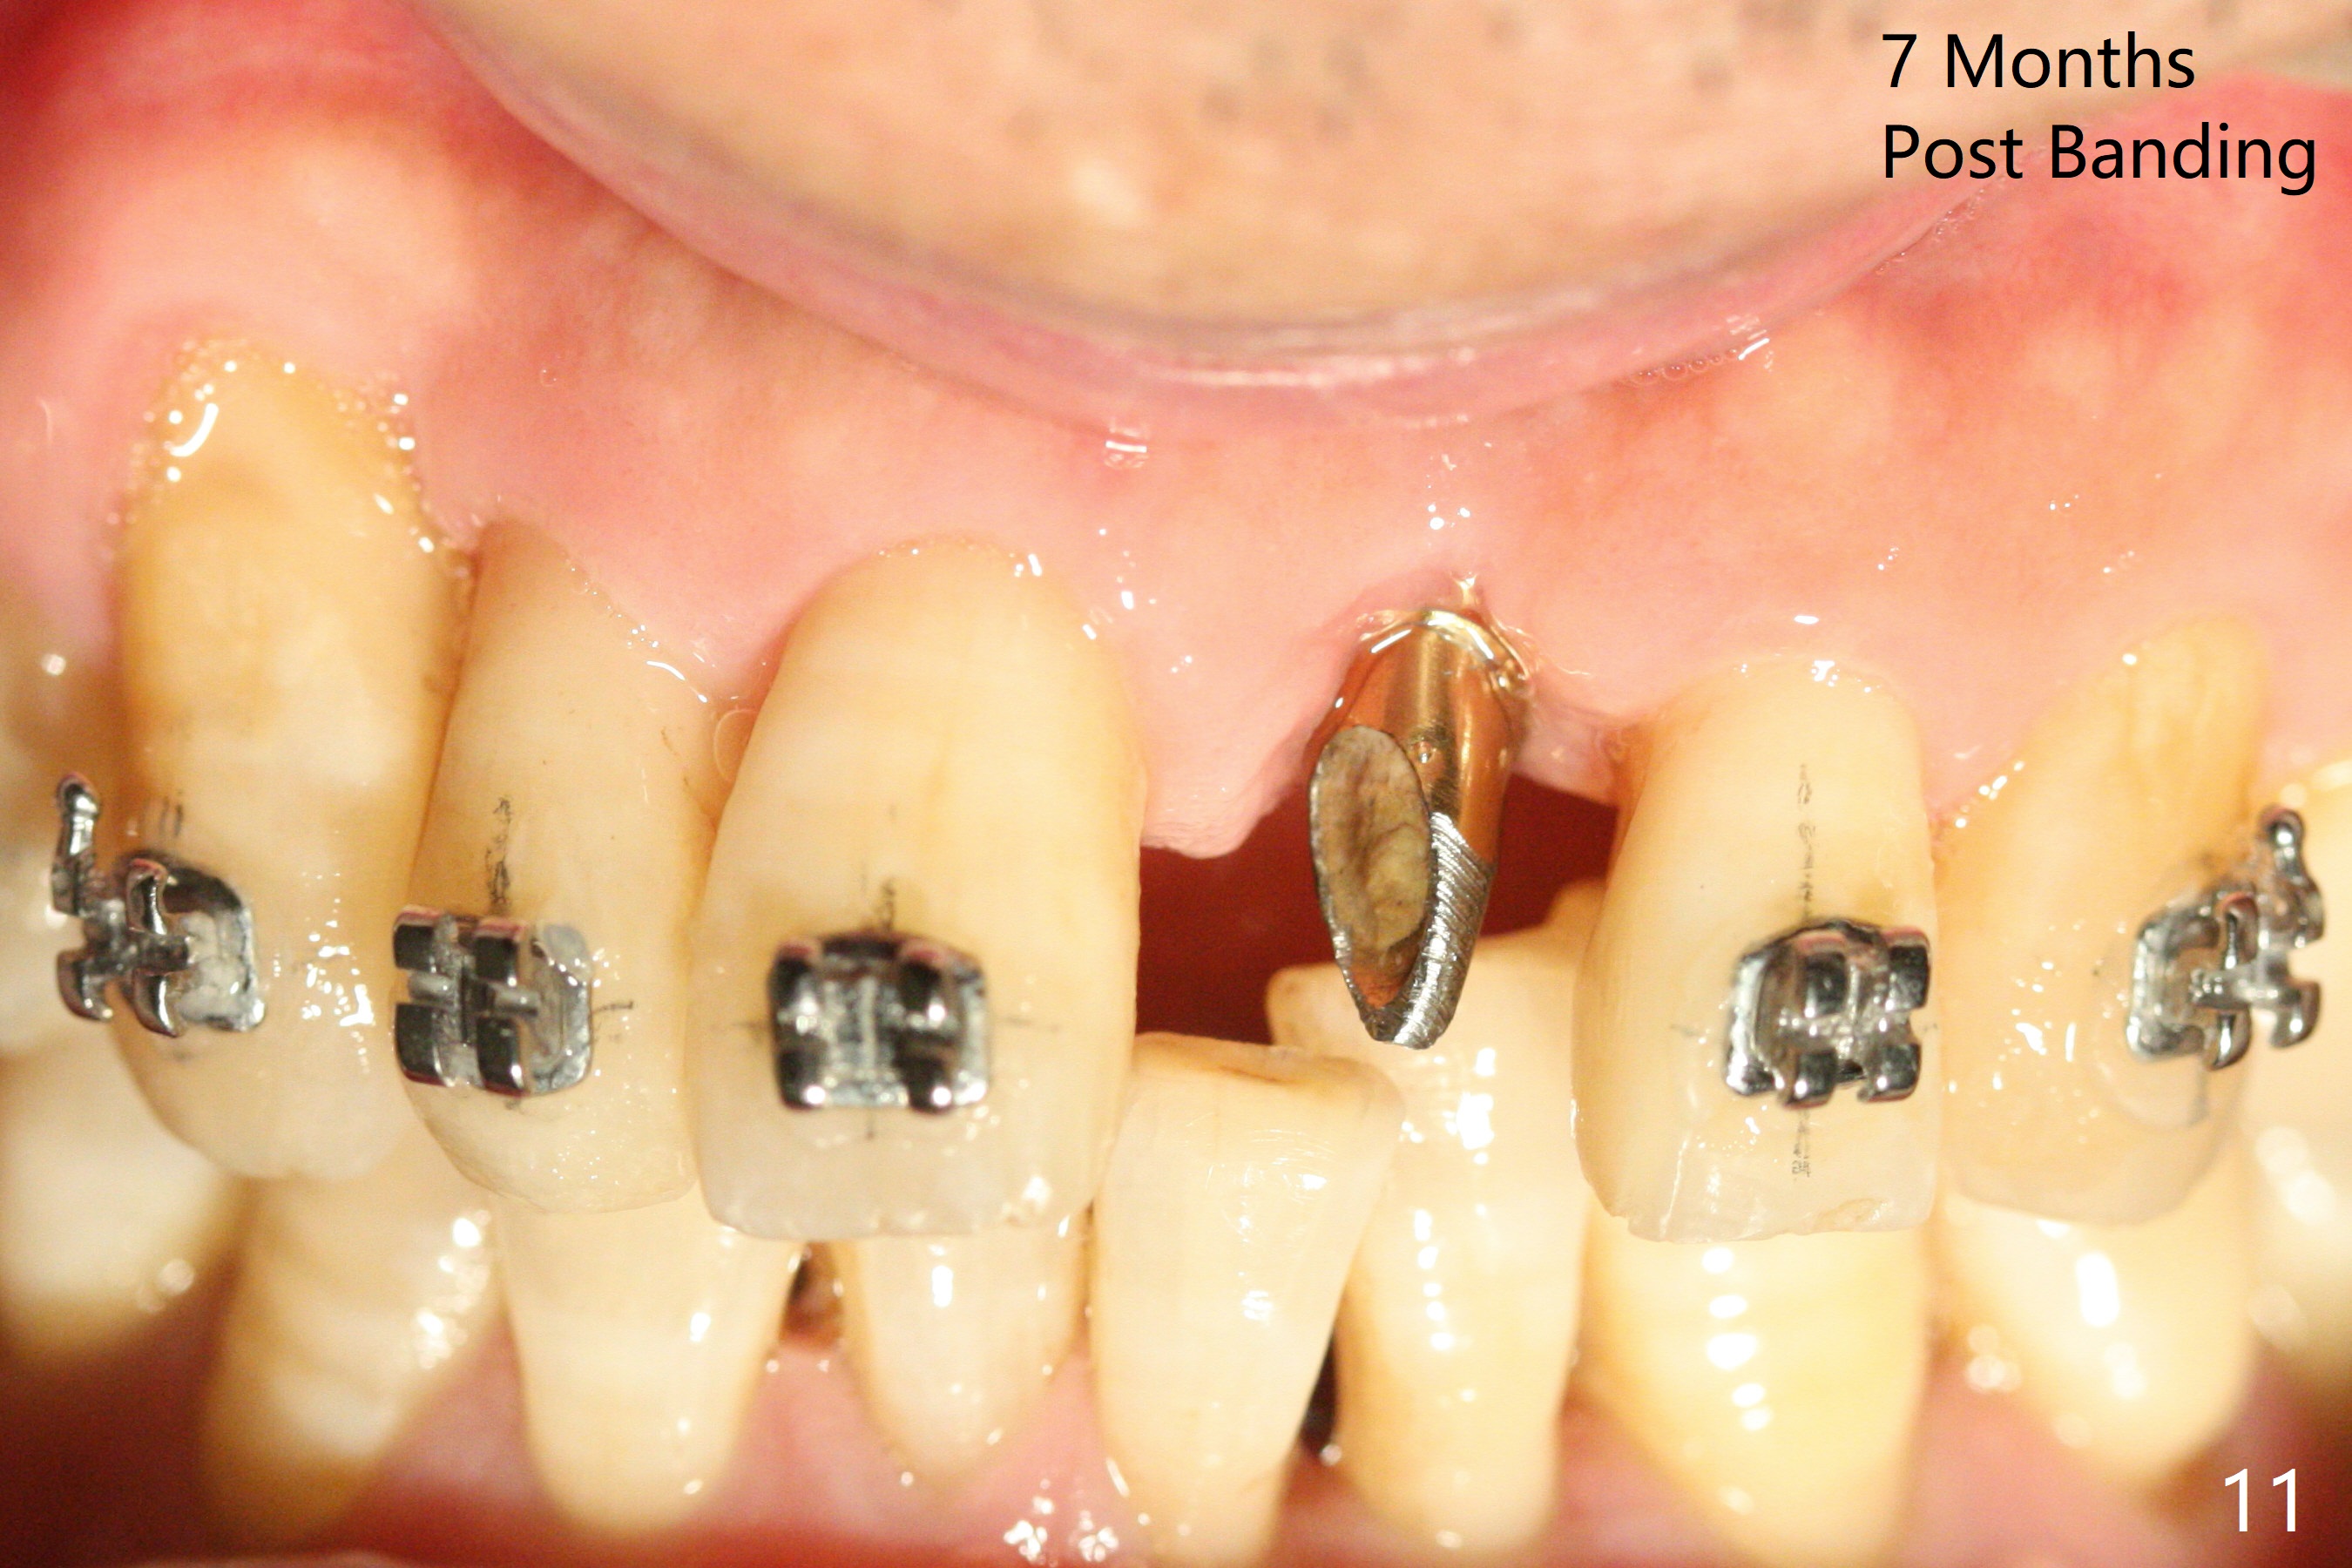

Nearly 7 months postop, the immediate provisional at UL1 is removed; with the mesial reduction of UL2 from 7 to 6 mm (Fig.1), an angled abutment is to be changed (4.5x15 degree, 2 mm cuff). A new provisional (Fig.2,3) co-incides with the facial midline. Brackets will be placed between UR4 to UL3 except UL2 (symptomatic once with chronic periodontitis) with initial proximal reduction between UR1-4 in preparation to correct cross bite of UR2. Twelve days later, the patient returns for UR5-UL3 bracketing after UR1-4 initial proximal reduction with 14 niti wire (Fig.4-6). UR1 moves mesial 20 days post open coil spring (Fig.7 arrow), while UL1 debracketes after permanent re-cementation of the temporary crown last visit (*, no re-bracketing, since it appears not essential). Before placement of 20 ss wire, diastemata are created by proximal reduction (Fig.8 *). In fact UR1 moves mesial, while UR3 does not move distal with the open coil. With placement of UR6 (implant) molar band, UR3 is distalized effectively. With sling shot, UR2 is almost labialized in one appointment (Fig.9). After consolidation of the diastemata between UR1-6 with power chains following UR2 cross bite correction (Fig.10), the restoration space for UL1 seems to be too large (Fig.11). Next visit, check the midlines, take 1-2 PAs for #7-9 and determine whether a straight abutment should be changed back and whether composite should be placed UR1 mesial to reduce the space. One week later, composite is added to the mesial surface of the tooth #8 to increase its width, while the provisional at #9 is relined to improve the interdental papilla (Fig.12). Minimal bone loss at UR2 is observed 8 months post banding (Fig.13), while the socket at UL1 seems to have healed except the most coronal 1 year 3 months postop (Fig.14 *). The margin of the abutment should be uneven, more coronal proximal than buccopalatal (Fig.15). The final crown has an open margin, partially due to less ideal trajectory (Fig.16 (black line: ideal trajectory, nearly 1 year 4 months postop)). Guided surgery could solve the problem. Sticky bone may restore the buccal plate defect. Die shows that the implant is palatally placed (Fig.17). CT will be taken to determine whether the implant perforates the palatal plate.